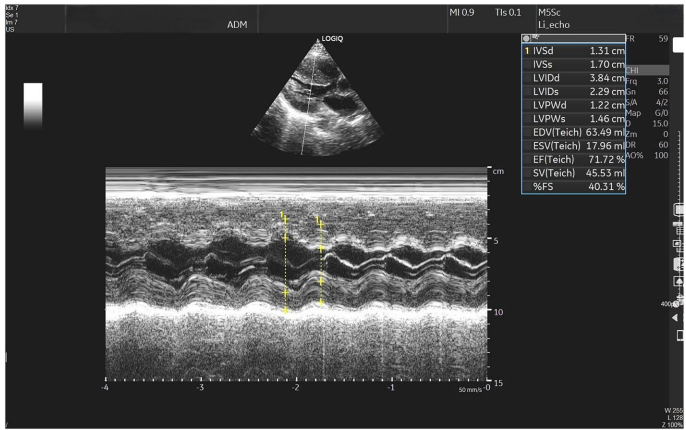

研究团队报道了一位40岁女性患者的惊险救治历程。患者突发严重胸痛伴休克,NT-proBNP(N末端脑钠肽前体)飙升至8588 pg/L,左心室射血分数(EF)骤降至40%。通过VA-ECMO与IABP构建"生命双保险"稳定循环后,CT发现右肾上腺4.7cm占位,24小时尿甲氧基肾上腺素(>2504μg/g Cr)等检测锁定嗜铬细胞瘤诊断。术后患者心功能完全恢复,验证了肿瘤切除对逆转心损伤的关键作用。

术后超声显示EF值回升至71%,心室径恢复正常